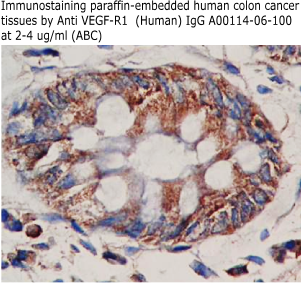

Code No.: A00114-06-100

Size: 100 ug

Price: $220.00 USD

Host: Rabbit

Antigen: human sVEGFR-1/sFlt-1 (335-654) Rec.

Ab Type: Polyclonal IgG

Purification: Protein A

Applications: E,WB

Working Dilution: 2 ug/ml)

Data Sheet: PDF |